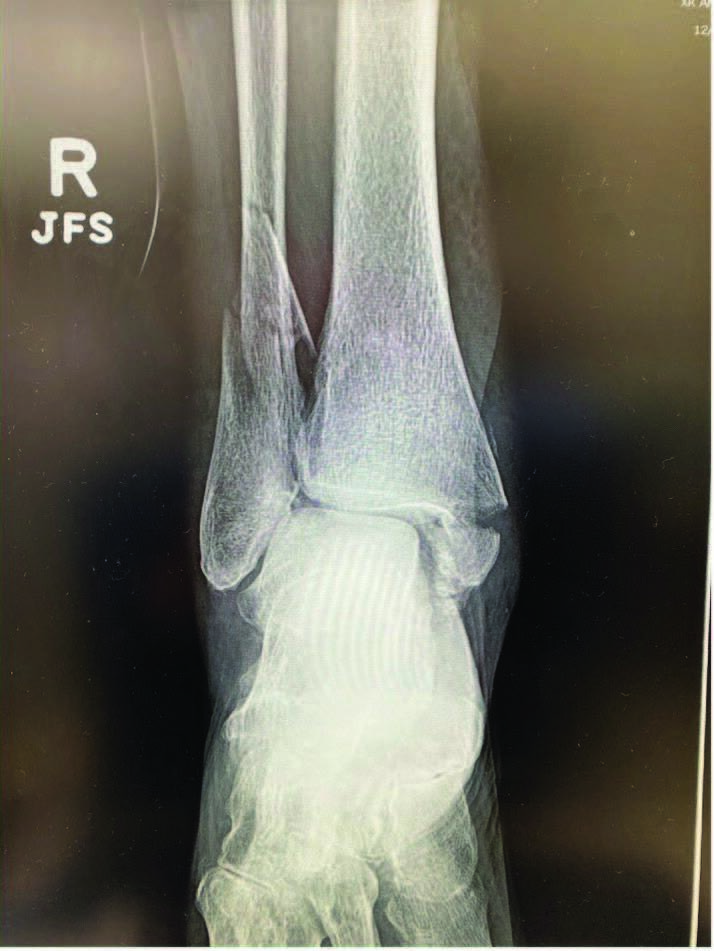

Pilon fractures are often secondary to high velocity injuries, which take a significant toll on the soft tissue envelope surrounding the ankle, and open fractures pose a specific clinical conundrum. The complexity of these injuries, in addition to the lack of muscle coverage and poor vascularity, makes these fractures especially difficult to treat. Traditionally, external fixation through Ilizarov methods has been the tried-and-true treatment for pilon fractures. We apply the tibial portion of the frame first, usually consisting of two or three rings. We then affix at least the proximal two rings to the tibia in accordance with the principles of Ilizarov techniques. Application of foot frames then takes place with two wires in the calcaneus and one wire in the talus, depending on surgical approach. A 5/8-ring around the hindfoot holds the calcaneal and talar wires and connects to the tibial portion by two threaded rods or struts. Reduction of the fracture takes place by distraction between the tibial segments of the frame and the foot segment through the threaded rods or struts. Insertion of olive wires can then compress the bony fragments. Fluoroscopy can then confirm the position of the wires and the reduction of the fractures. Patients are then partial weight-bearing with the external fixator in place for up to six months at times, to allow for proper healing. Surgeons can combine this method with internal fixation, and often times, both can compliment each other.

A portion of the literature calls for ankle arthroscopy for additional visualization of the articular surface and to further ensure adequate reduction.3 This specific technique is typically used in high-risk patients when plating or intramedullary fixation is not an option and soft tissue trauma is advanced. A recent study retrospectively assessed 169 distal tibial fractures, of which 28 percent were open and treated with ring external fixation. They noted that 98 percent of the fractures united at a median of 166.5 days and reported few serious complications.3 The authors limit the choice for fine wire fixation in distal tibial intra-articular fractures to open, or infected non-union cases.